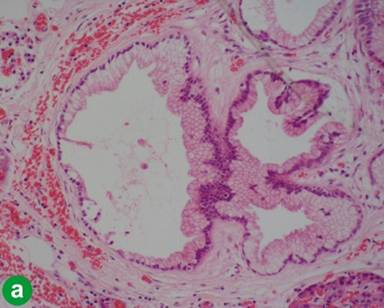

The patient underwent a pylorous preserving pancreaticoduodenectomy and histology confirmed a well differentiated adenocarcinoma arising in the mucosa of ampulla of Vater, with invasion of the seromuscularis externa, soft tissue and perineural space of pancreaticoduodenal sulcus and juxtaduodenal pancreas. Bile duct, duodenal, pancreatic and vascular resection margins, and pancreaticoduodenal lymph nodes were free of tumour. Immunohistochemistry revealed positivity for cytokeratin (CK) 7 and mucin core protein (MUC) 1, and negativity for MUC2 and CK20, appearances consistent with the pancreatobiliary subtype of ampullary carcinoma (Figure 1). Interestingly foci of mucinous metaplasia, of pancreatic duct epithelium corresponding to PanIN-1A, of the pancreatic duct epithelium with patchy chronic pancreatitis and acinar atrophy, were observed at the pancreatic resection margin (Figure 2a). The tumour was characterized as pT3, pN0, pM0.

Figure 1. Histopathology of ampullary, lung, and pancreatic cancers. All three tumours consist of well differentiated adenocarcinoma forming papillo-tubular glandular structures. All tumours have an immunophenotype CK7+/CK20-/MUC1+/MUC2-. All images: x200. |

After an uneventful postoperative recovery and discharge on day 14, she received 12 cycles of adjuvant gemcitabine/oxaliplatin chemotherapy. At a follow-up of 52 months, without elevation in tumour markers (CA 19-9 less than 30 U/mL), a surveillance CT demonstrated a speculated 11x12 mm nodule in the left upper lobe, confirmed also with a single 18F fluorodeoxyglucose (FDG) avid lesion on positron emission tomography (PET). She underwent a left upper lobe wedge resection, which revealed a 8 mm, nodular adenocarcinoma with immunohistochemical staining showing strong positivity of the tumor cells for CK7 and MUC1 but CK20, MUC2 and thyroid transcription factor-1 negative (Figure 1); an immunoprofile again consistent with the diagnosis of metastatic adenocarcinoma. Fourteen months after the wedge resection, CA 19-9 level rose to 40 U/mL and subsequent imaging revealed a relapse of the pulmonary metastasis. The patient was commenced on neo-adjuvant chemotherapy (6 cycles of gemcitabine/capecitabine), and underwent a left pneumonectomy 76 months after index procedure.

Finally 7 years after the initial pylorous-preserving Whipple’s for ampullary cancer, the patient developed a further single, FDG avid lesion in the tail of the pancreas, which led to completion pancreatectomy and splenectomy, when histology confirmed a 28 mm well-differentiated ductal adenocarcinoma, with infiltration of the peripancreatic adipose tissue and perineural spaces. Resection margins were clear and a single lymph node was tumor free. Tumour cells had the immunophenotype CK7+/CK20-/MUC1+/MUC2-, same as the ampullary and lung tumors (Figure 1). Interestingly, small pancreatic ducts around the tumour showed dysplastic features corresponding to PanIN-2 or -3 in places (Figure 2).